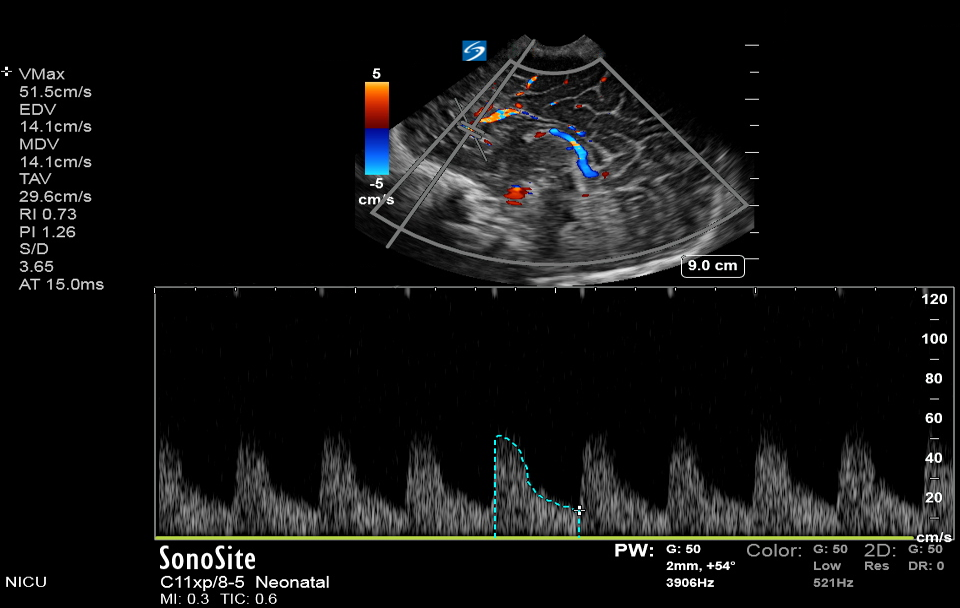

Neonatology Doppler Study of Anterior Cerebral Artery Image